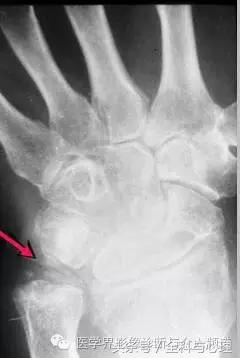

尺骨三角纤维软骨复合体钙化